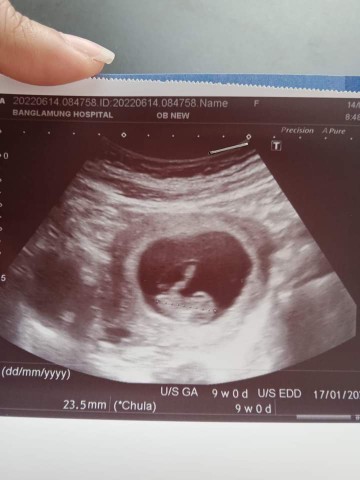

ทีม17มกราคม66จ้า บ้านนี้แพ้หนักมาก ไปซาวด์ตอนน้อง9wค่ะแม่